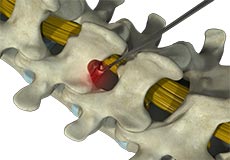

Epidural Steroid Injections

Epidural steroid injection (ESI) is a minimally invasive approach to treat inflammation of spinal nerves that causes pain in the neck, arms, back and legs. This technique may help relieve back pain in conditions such as spinal stenosis, spondylolysis or herniated discs. In this technique, the steroidal medications are injected into the spinal canal so as to pass down to the inflamed spinal nerve through the epidural space which lies between the covering of the spinal cord and the vertebrae. An ESI contains a corticosteroid medication along with an anesthetic agent which can reduce the inflammation and pain.